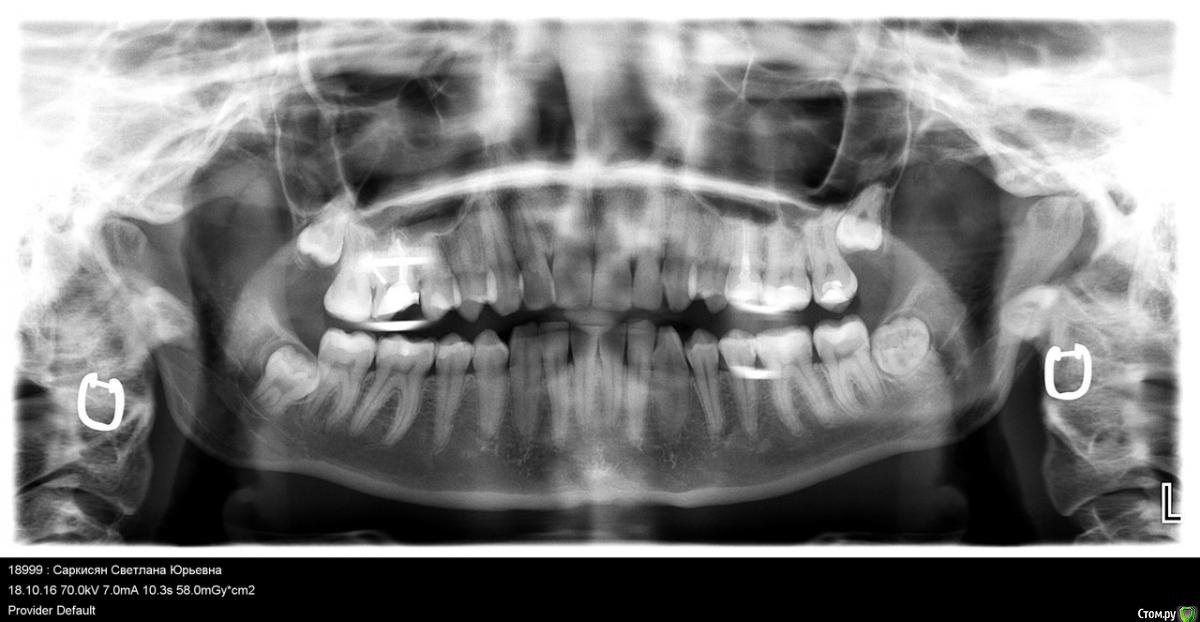

Setasy Опубликовано 14 декабря, 2016 Поделиться Опубликовано 14 декабря, 2016 (изменено) Здравствуйте! Очень нужен совет. В июле мне пролечили глубокий кариес 6-ки сверху слева. Примерно в то же время лечили и 6-ку снизу, там никак не могли подобрать нормально пломбу, больно было на ней жевать, пока не поставили ветример. Таким образом, я не могла полноценно кушать на левой стороне и проверить, все ли в порядке с верхним 6 зубом. Когда наконец смогла это делать, стала ощущать постоянный дискомфорт при жевании твердой пищи ближе к 5 зубу. Обратилась к другому доктору, он снял пломбу, думали, может что-то проседает там, ничего не изменилось. Когда он снял в следующий раз всю реставрацию, сказал, что видит там трещину корня, но не был уверен. У меня в тот же день начался острый пульпит, сильнейшая боль. Каналы мне врач пролечил, с коффердамом, с бинокулярами, все как положено, заложил кальций. Но есть на зубе по-прежнему невозможно было. Так не болит, но даже минимальная нагрузка (мягкой пищей) и все, чувствуется языком снова боль, неприятно дотрагиваться. Врач от меня отказался, говорит, что все правильно делает и не знает, почему у меня не проходит. Наверное все-таки трещина, тогда любое лечение несостоятельно. Обратилась еще к одному врачу, она рассверлила временную пломбу, промыла хлоргексидином каналы и заложила какую-то йодовую пасту. Трещины не увидела. После этого вообще до зуба не дотронуться было, все вокруг было очень болезненно и как будто камней наложили. На 4 день это острое состояние прошло и вернулось все то же, что и было. До зуба больно дотрагиваться языком и невозможно есть. Сегодня мне сделали КТ. Врач, смотревший КТ, сказал, что трещины корня не видит (хотя я прочла, что трещину корня по КТ вообще нельзя увидеть). Якобы надо расширять каналы. Что имелось ввиду, непонятно. Каналы мне точно лечили хорошо (4 штуки нашли). КТ прилагаю https://yadi.sk/d/_2x90byG33Wtt8 Снимки есть до лечения каналов. Прикладываю...и также ортопонарама. Я планирую беременность и мне хочется как можно быстрее разобраться с этим зубом. Можно ли оставить пока так как есть (допустим, если там трещина все-таки) или необходимо удаление? Если удалять, возможно ли сразу поставить имплант при удалении или нужно ждать? Ну и вообще хотелось бы услышать мнение по поводу ситуации, что может быть и что делать. Спасибо!!!!!!!! Изменено 14 декабря, 2016 пользователем Setasy Ссылка на комментарий